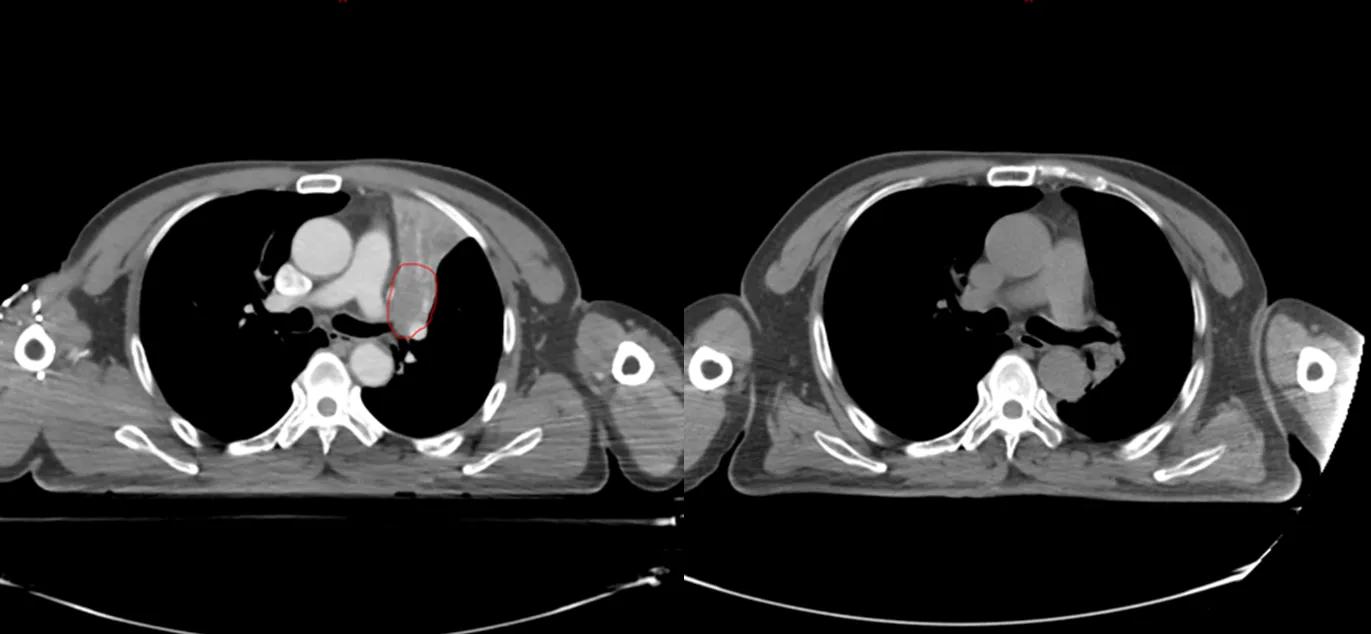

与这些名人患肺癌的同时,笔者治好了至少5位晚期肺癌病人(见下图CT片显示的肿瘤)。笔者病人有咳嗽,咯血,胸痛,胸闷,气急等症状,病人家属知道亲人是晚期肺癌,没有抱多大希望,治疗的目的只是想减轻一些症状,延长生命。经过笔者的精心治疗,2例现已活了5年多,2例已活过3年多,1例已活过2年多。治疗时年龄最大有82岁,最小年龄51岁,他们现在都生活得很好,甚至一个来自江西农村的病人一直在田地里干重体力农活。

治疗前后CT对比,红色为肿瘤(左),治疗后肿瘤消失(右)